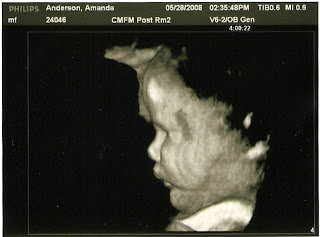

I had another in-depth ultrasound today at 35 weeks pregnant. Baby seems to be doing well but growing quite large. By ultrasound estimates, this little one is over 6 1/2 pounds already, maybe close to 7. Because of baby's large size, they checked my glucose which was borderline high. Therefore, I have to do another glucose tolerance test tomorrow as it appears that I may have developed gestational diabetes :( . Dr. said that we will probably have to proceed with the c-section in just over 2 weeks due to baby's large size and my increased amount of amniotic fluid (risk of cord prolapse if my water broke spontaneously). Good news is that baby is doing lots of practice breathing, so s/he should be ready for this great big world soon!! We'll keep you posted!